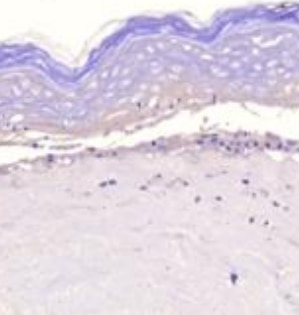

View Larger

MMP‑1 in Human Ovarian Array. MMP-1 was detected in immersion fixed paraffin-embedded sections of human ovarian array using Mouse Anti-Human MMP-1 Monoclonal Antibody (Catalog # MAB901) at 25 µg/mL overnight at 4 °C. Tissue was stained using the Anti-Mouse HRP-DAB Cell & Tissue Staining Kit (brown; Catalog # CTS002) and counterstained with hematoxylin (blue). Lower panel shows a lack of labeling if primary antibodies are omitted and tissue is stained only with secondary antibody followed by incubation with detection reagents. View our protocol for Chromogenic IHC Staining of Paraffin-embedded Tissue Sections.